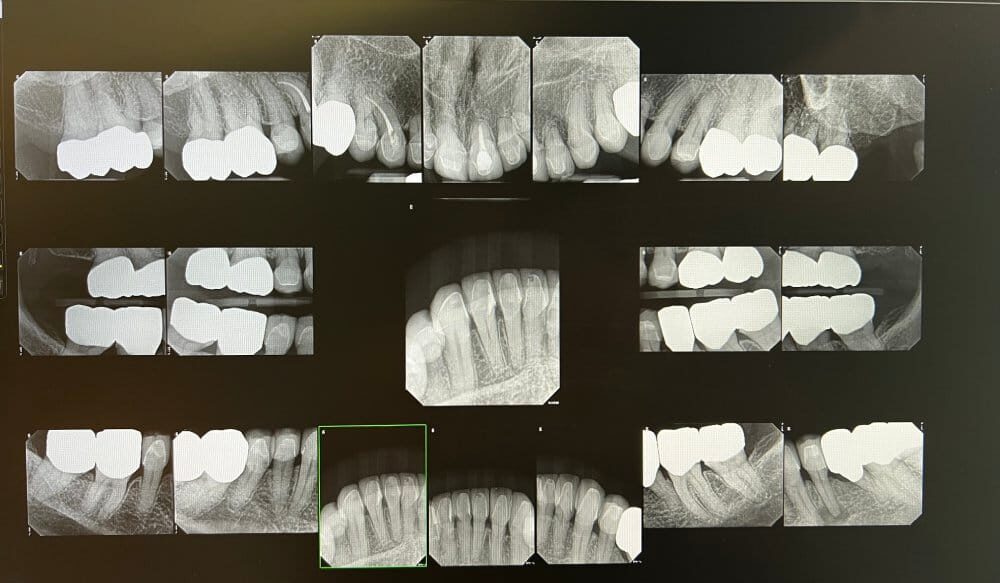

Digital X-Rays

As part of your ongoing preventive care, x-rays are recommended once a year during your six-month checkup and are taken when you present with a dental concern, pain, or emergency. MacPhail Signature Smiles uses digital x-rays that record images from a small sensor placed in your mouth. Digital x-rays produce clearer and more precise images in less time than traditional dental radiographs that require processing time and are not as clear. The images are sent to computer software to be viewed in digital format. Digital x-rays are incredibly safe and emit significantly less radiation than older x-ray units. With digital x-rays, Dr. MacPhail can see exactly what’s occurring between your teeth and under the gum line along the jawbone, including roots of your teeth.